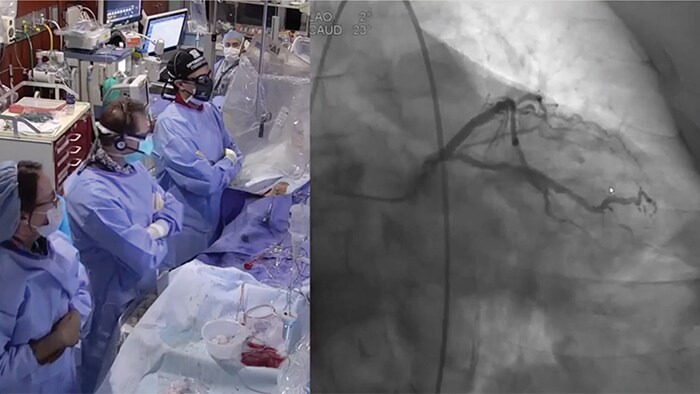

Ultra-low contrast coronary angiography and zero-contrast percutaneous coronary intervention for prevention of contrast-induced nephropathy: step-by-step approach and review

Prof. Dariusz Dudek

President EAPCI ESC

Jagiellonian University

Krakow, Poland

New invasive imaging techniques and co-registration software allows PCI to be performed with limited amounts of contrast, even with zero-contrast use, to reduce the risk of CI-AKI for all patients, and especially those with renal insufficiency.